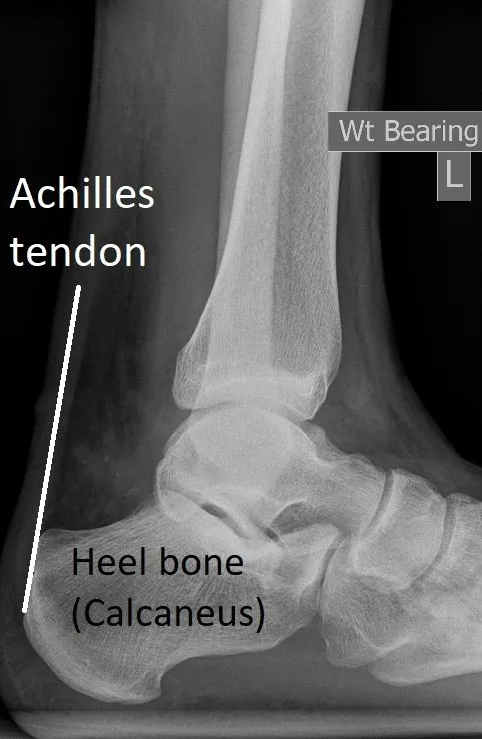

Achilles Insertional Tendinopathy and Spurs

This form of the condition occurs at

the insertion

(attachment) of the Achilles tendon on to the heel bone (calcaneus). It is associated with aging, obesity and sero-negative inflammatory arthritis (psoriatic arthritis, ankylosing spondylitis, DISH, etc).

Most people also develop bony heel spurs

that grow up inside the tendon from the calcaneus (see images).

Lateral heel x-rays show insertion bone spurs. Ultrasound and MRI look closely at the tendon.